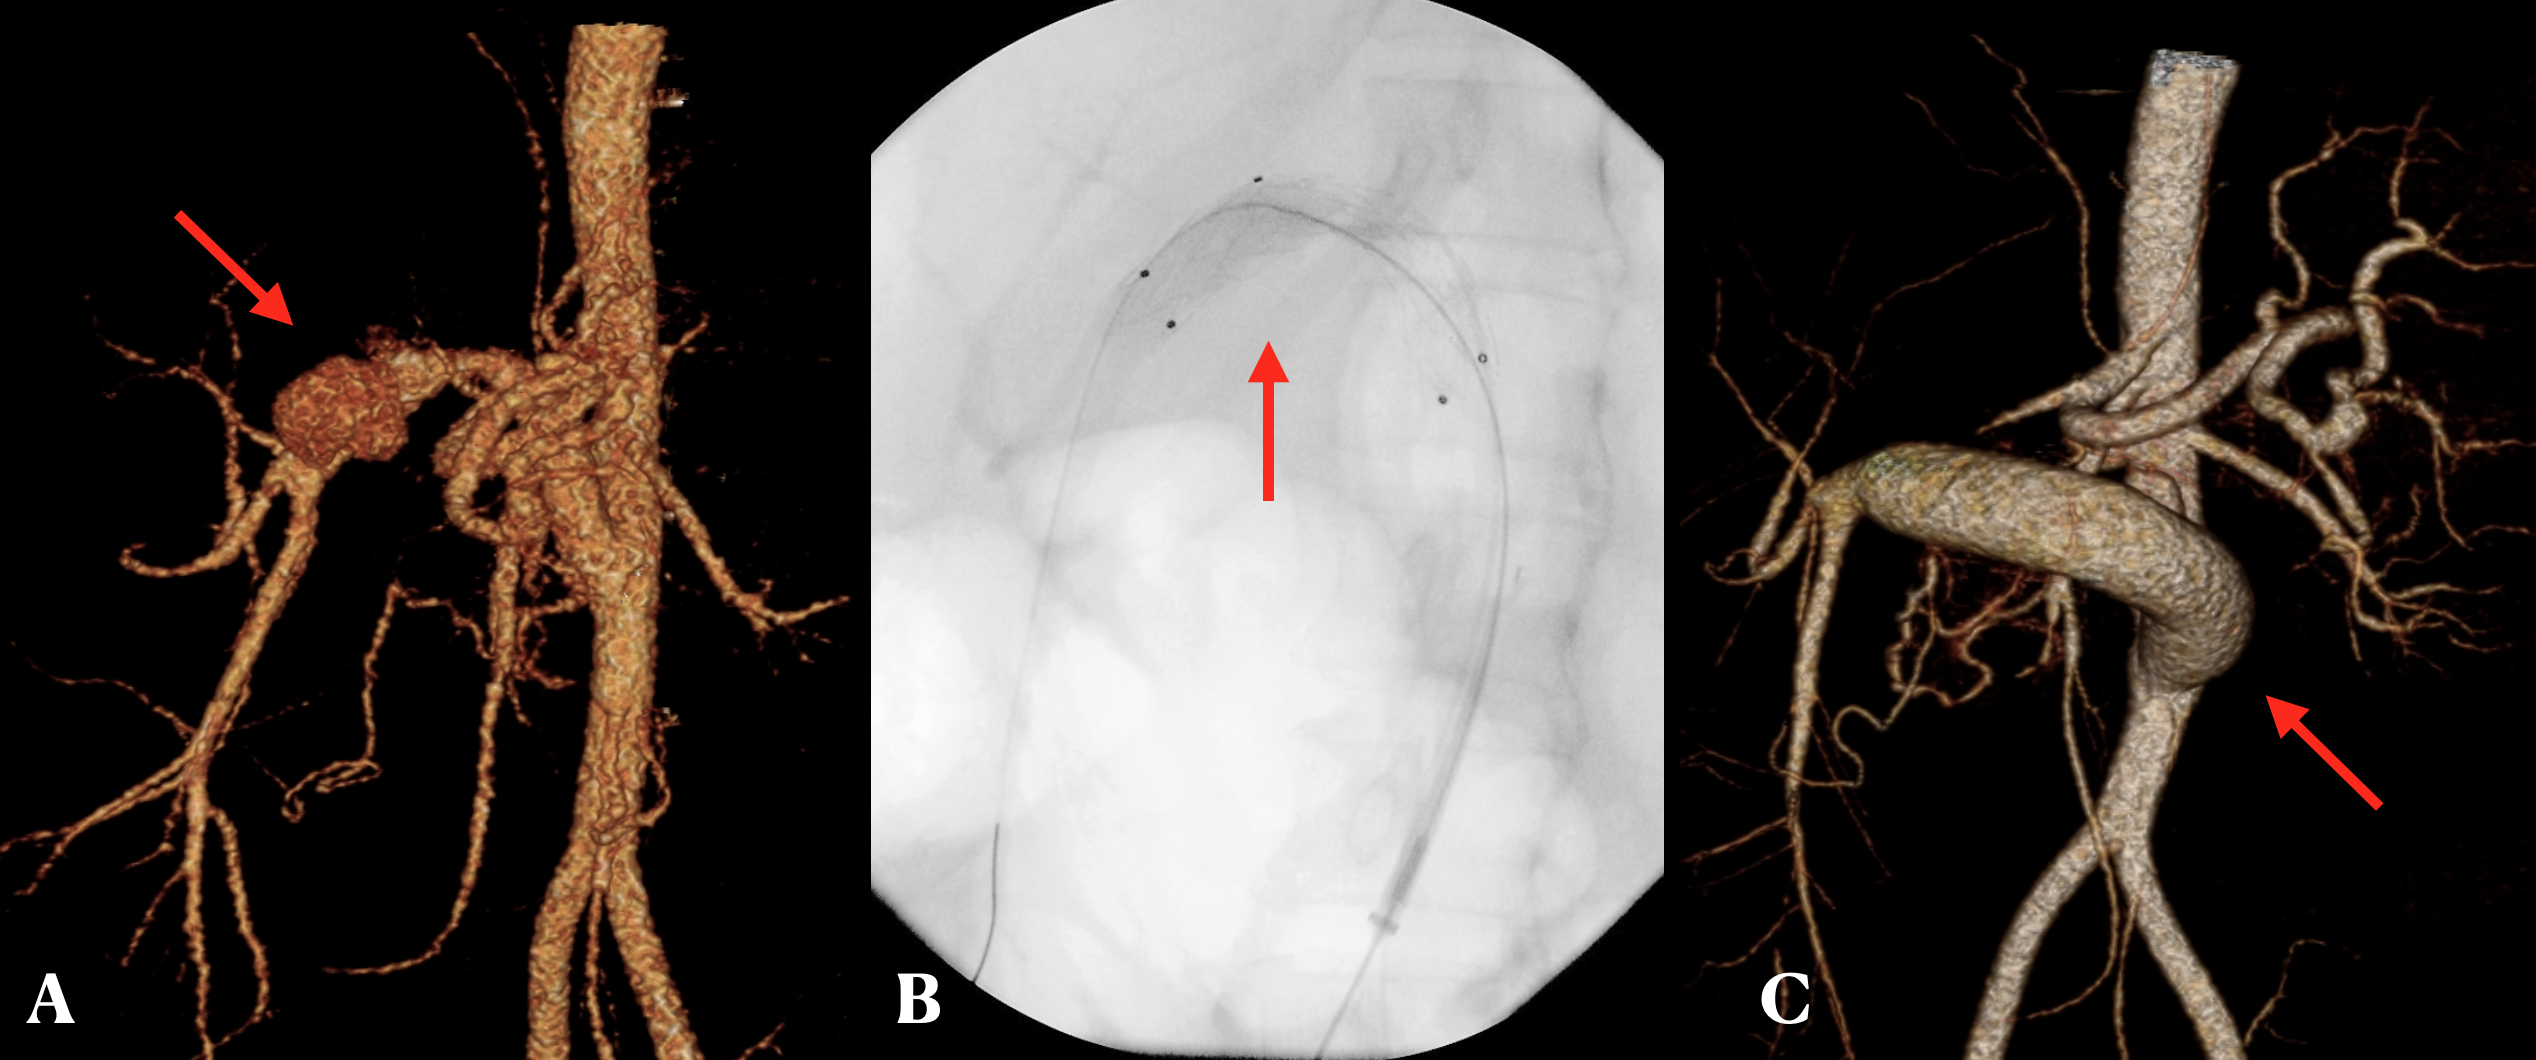

The two recurrences were clinically more subtle, identified incidentally on a CT in one case or associated with abdominal discomfort and maelena in the other. Apart from targeted antibiotic and antifungal treatment, management strategy pivoted around endovascular stent grafting (ESG) followed by a subtotal resection of the aneurysmal vessel and creation of a new conduit (Figure 2) using third party vascular homograft.